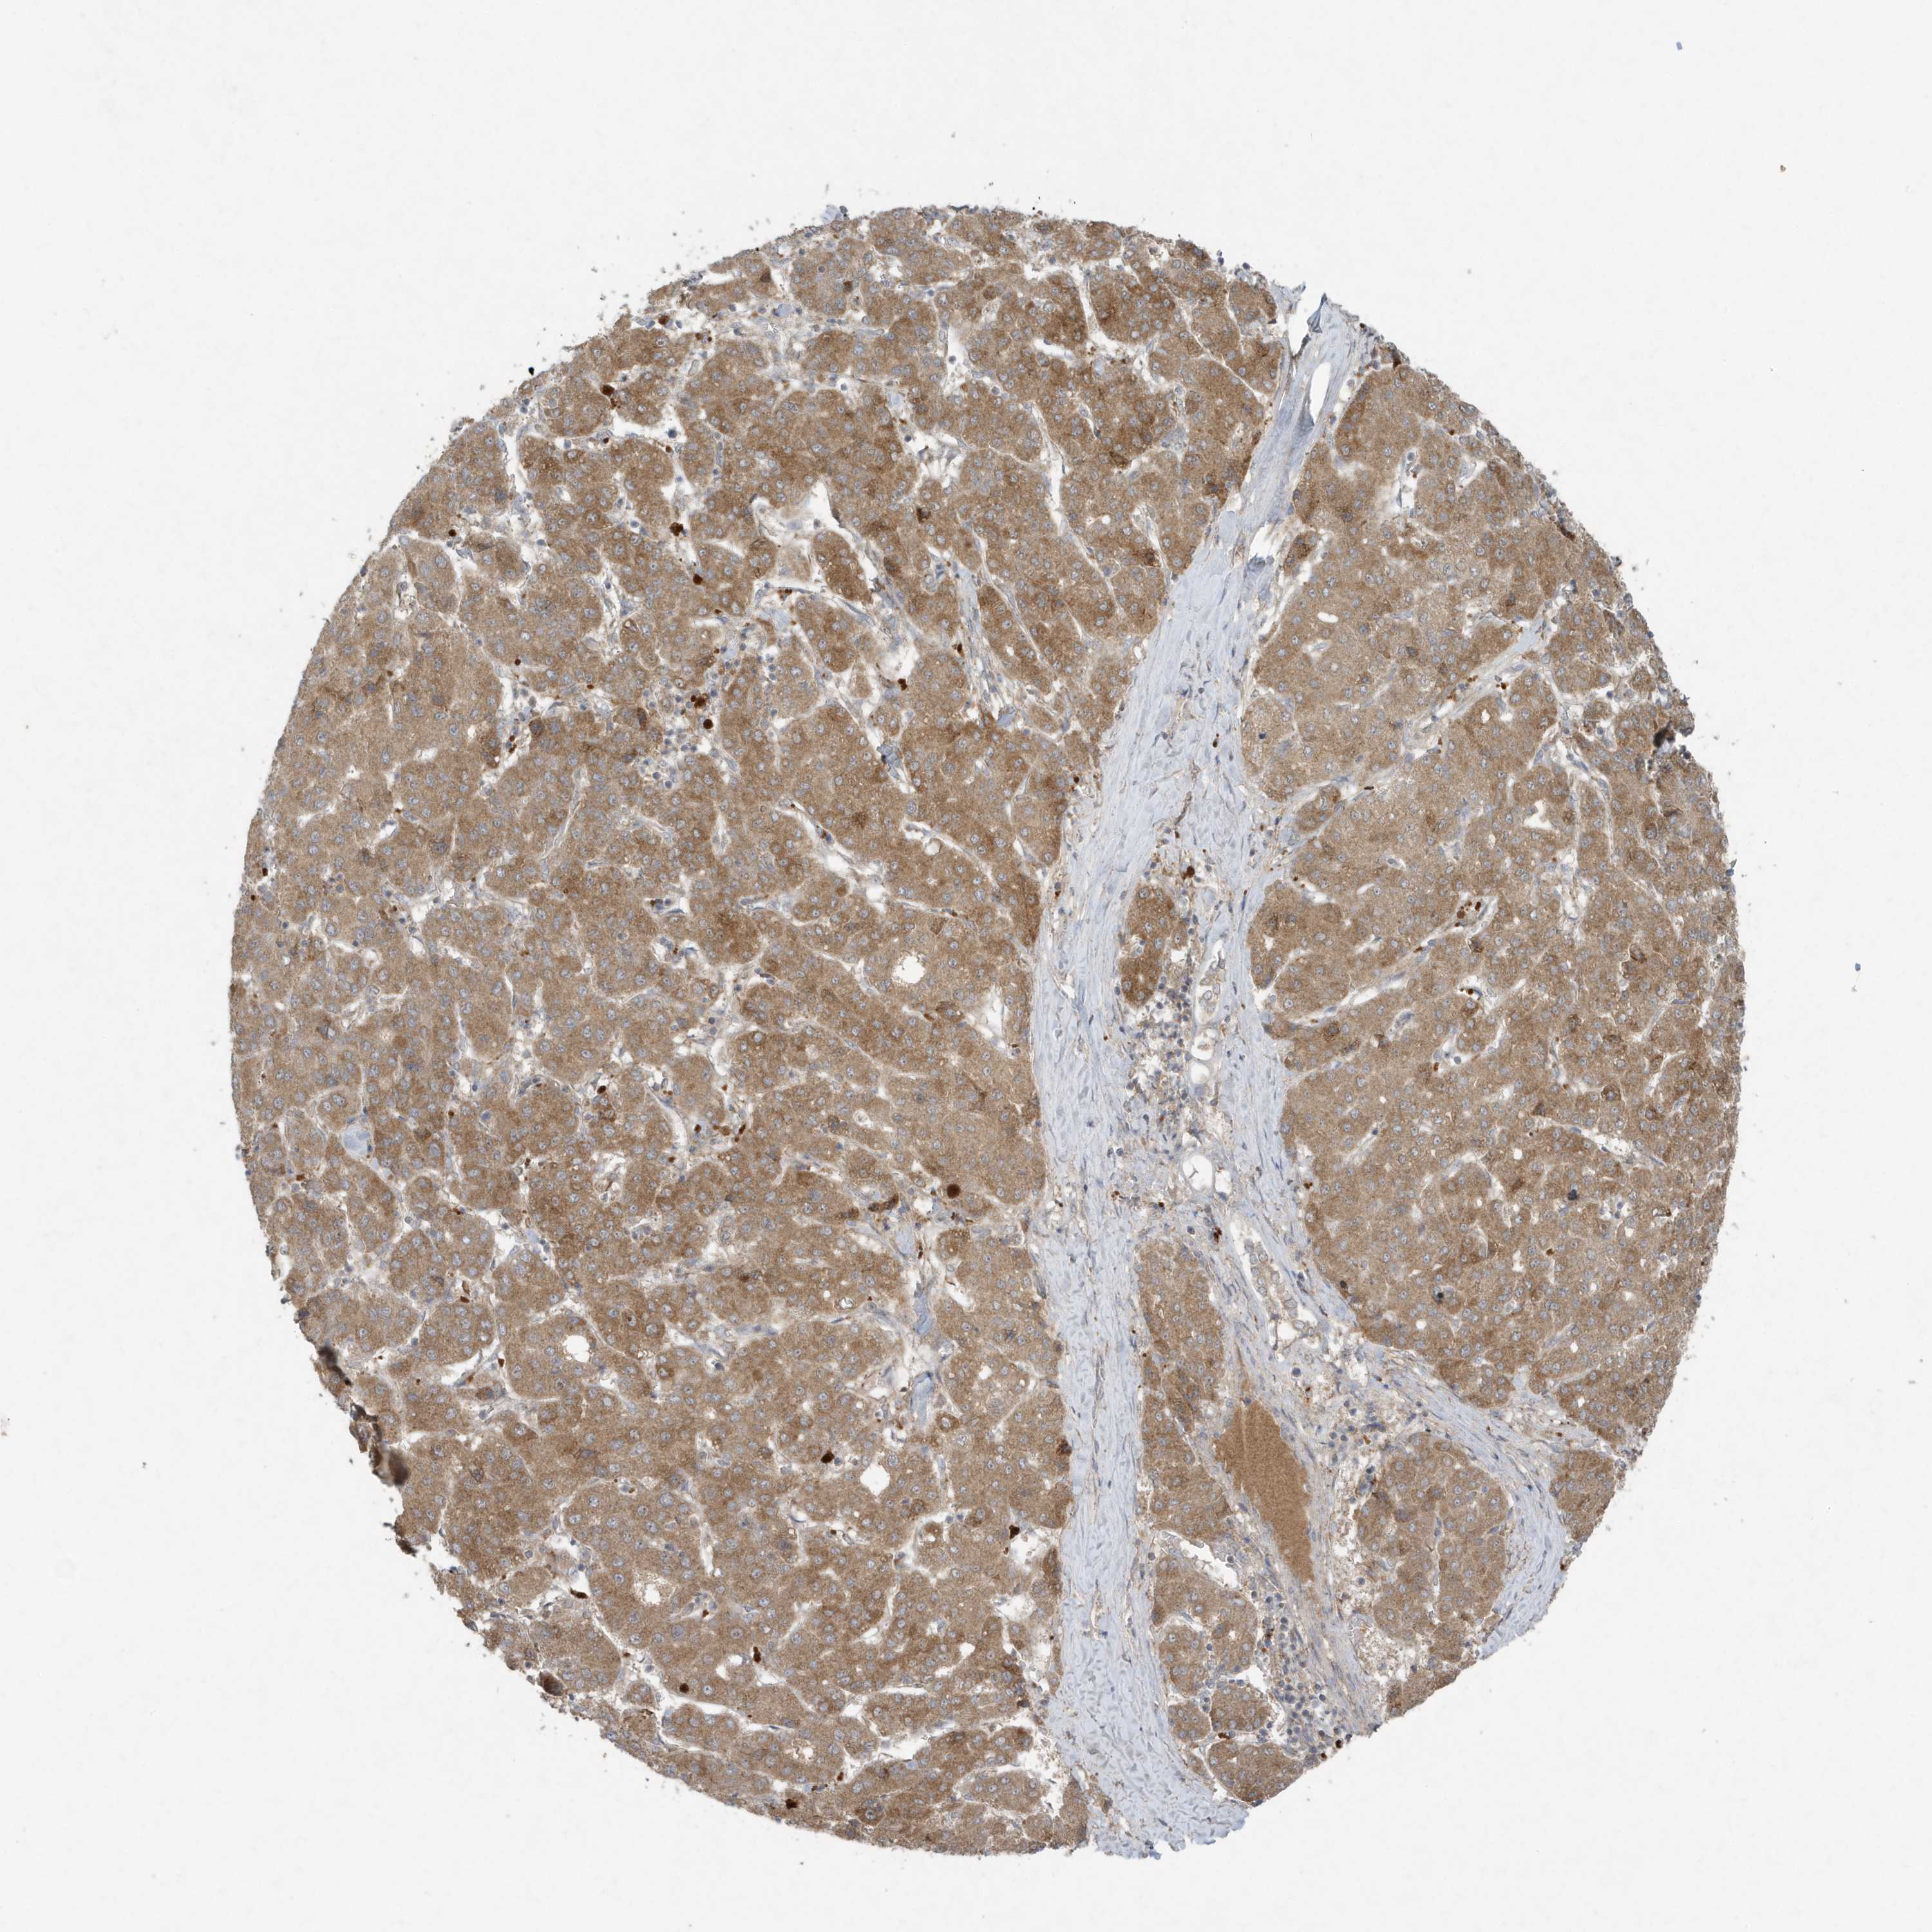

LIVER CANCER - Protein expressioni

A mouse-over function shows sample information and annotation data. Click on an image to view it in a full screen mode. Samples can be filtered based on level of antibody staining by selecting one or several of the following categories: high, medium, low and not detected. The assay and annotation is described here.

Note that samples used for immunohistochemistry by the Human Protein Atlas do not correspond to samples in the TCGA dataset.

Antibody stainingi

Antibody staining in the annotated cell types in the current human tissue is reported as not detected, low, medium, or high, based on conventional immunohistochemistry profiling in selected tissues. This score is based on the combination of the staining intensity and fraction of stained cells.

Each image is clickable and will lead to virtual microscopy that enables deeper exploration of all samples and also displays staining intensity scores, fraction scores and subcellular localization as well as patient and tissue information for each sample.

Antibody HPA011338

Antibody CAB026172

Staining

High

Medium

Low

Not detected

Intensity

Strong

Moderate

Weak

Negative

Quantity

>75%

75%-25%

<25%

None

Location

Nuclear

Cytoplasmic/membranous

Cytoplasmic/membranous,nuclear

Cholangiocarcinoma

Carcinoma, Hepatocellular, NOS